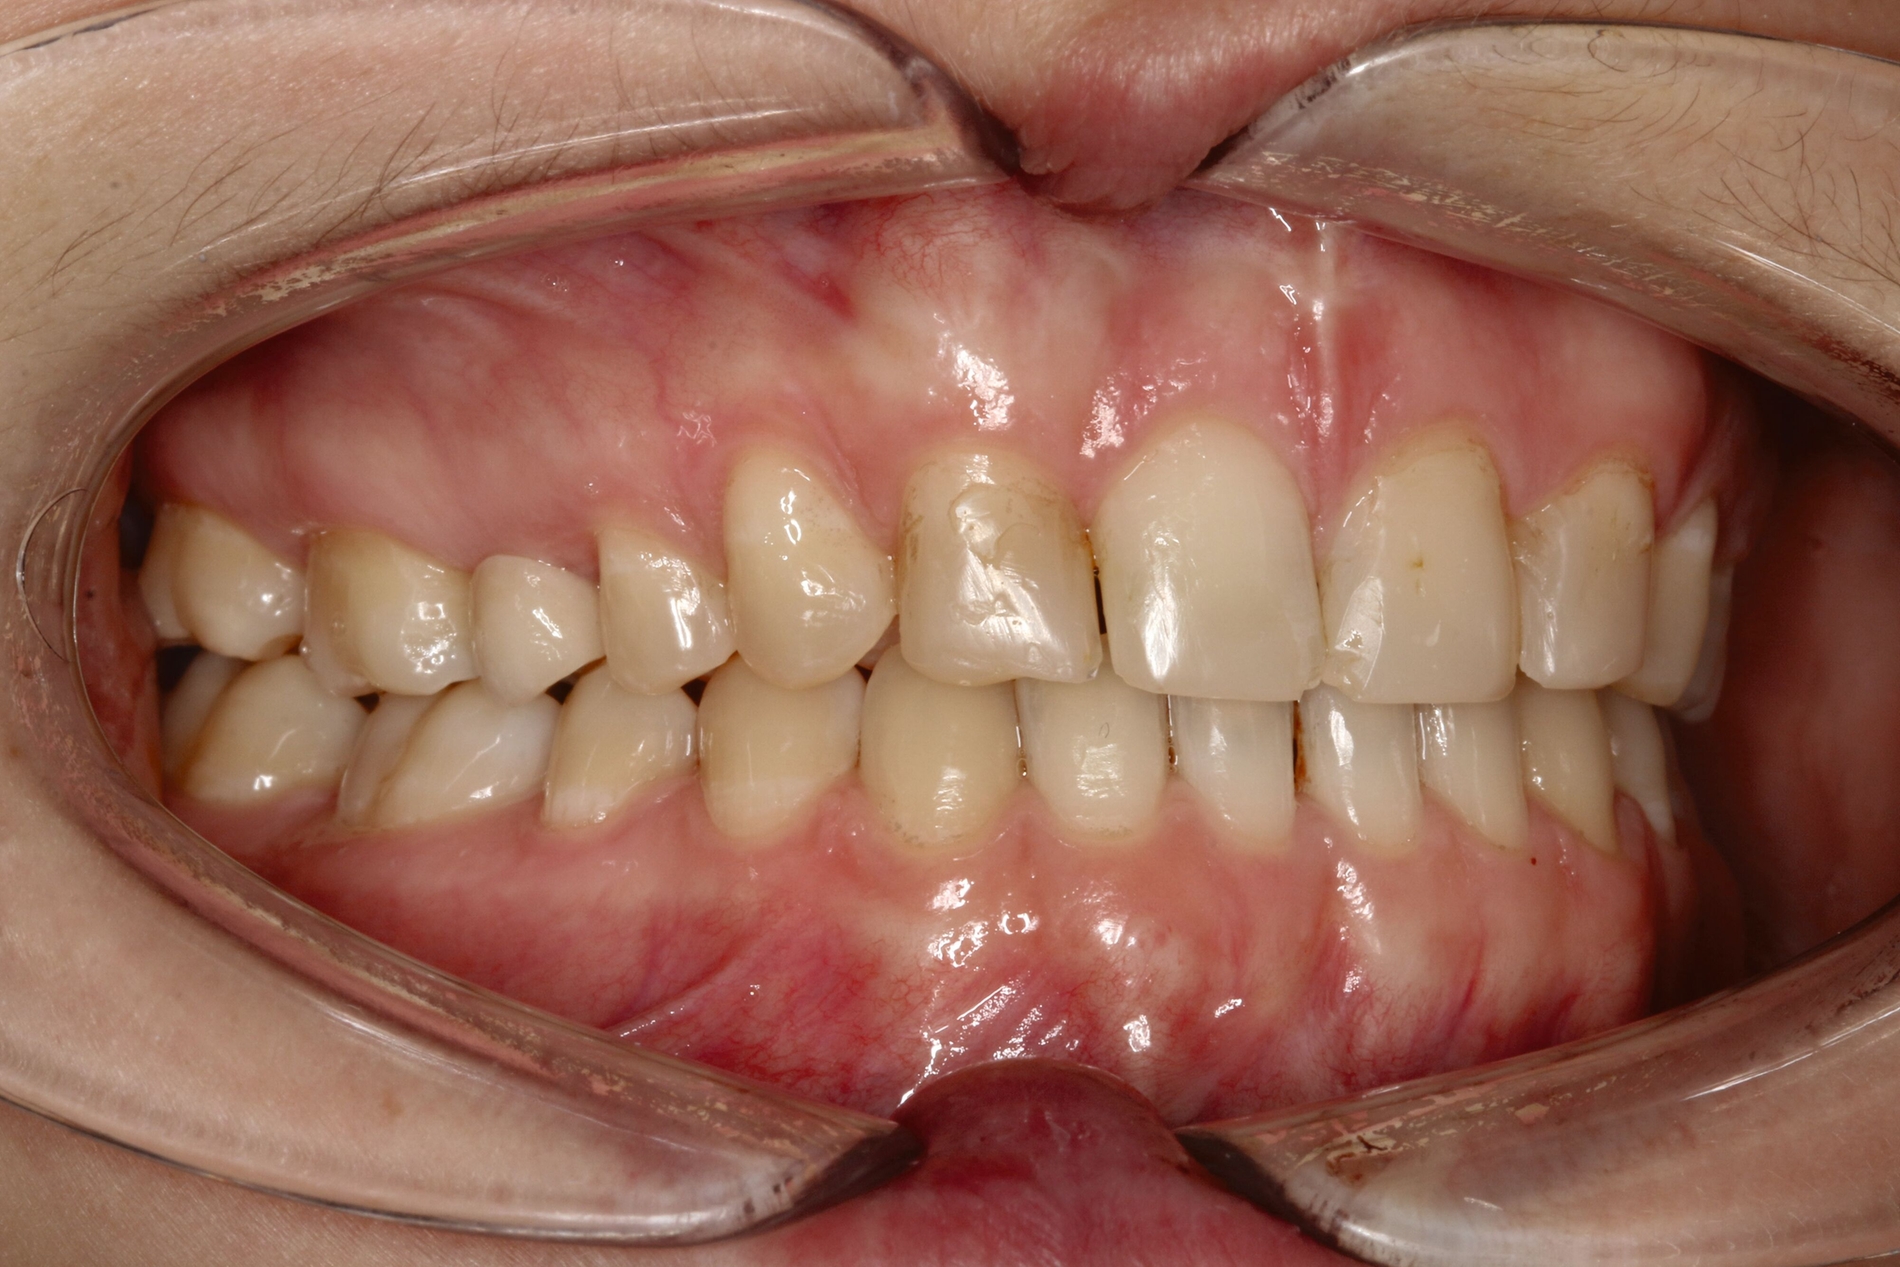

Bei dem gut zwölfjährigen Mädchen sind die seitlichen oberen Schneidezähne (Zähne 12 und 22) nicht angelegt. Zusätzlich zeigten sich verlagerte zweite obere Prämolaren.